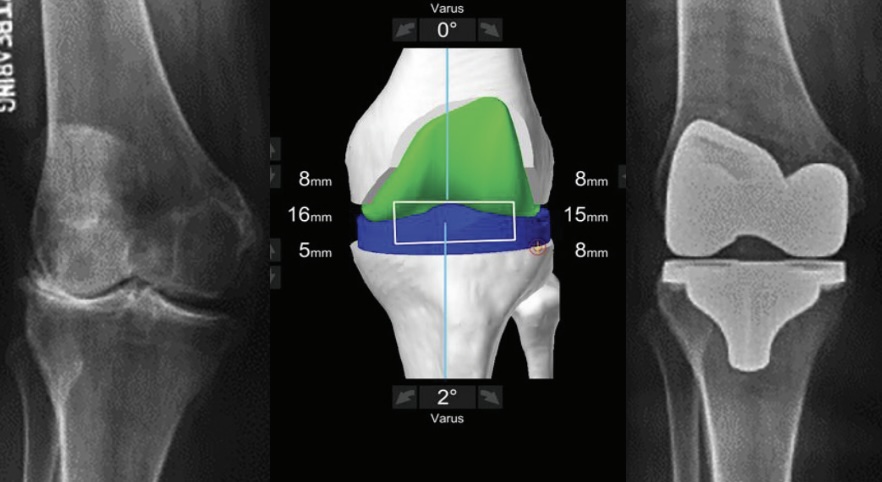

Una tomografía computada crea un modelo 3D exacto de tu cadera o rodilla. No un modelo genérico, sino TU anatomía específica, con cada detalle capturado.

El cirujano puede visualizar tu articulación en tres dimensiones, rotar el modelo, medir con precisión milimétrica, y diseñar el procedimiento óptimo para tu caso único.

El brazo robótico guía cada corte con precisión de medio milímetro. Crea un límite virtual que físicamente no puede ser traspasado, garantizando que cada corte sea exactamente como se planificó.

Un implante posicionado con precisión perfecta en el punto biomecánico ideal para tu anatomía. No aproximadamente bien. Perfectamente.